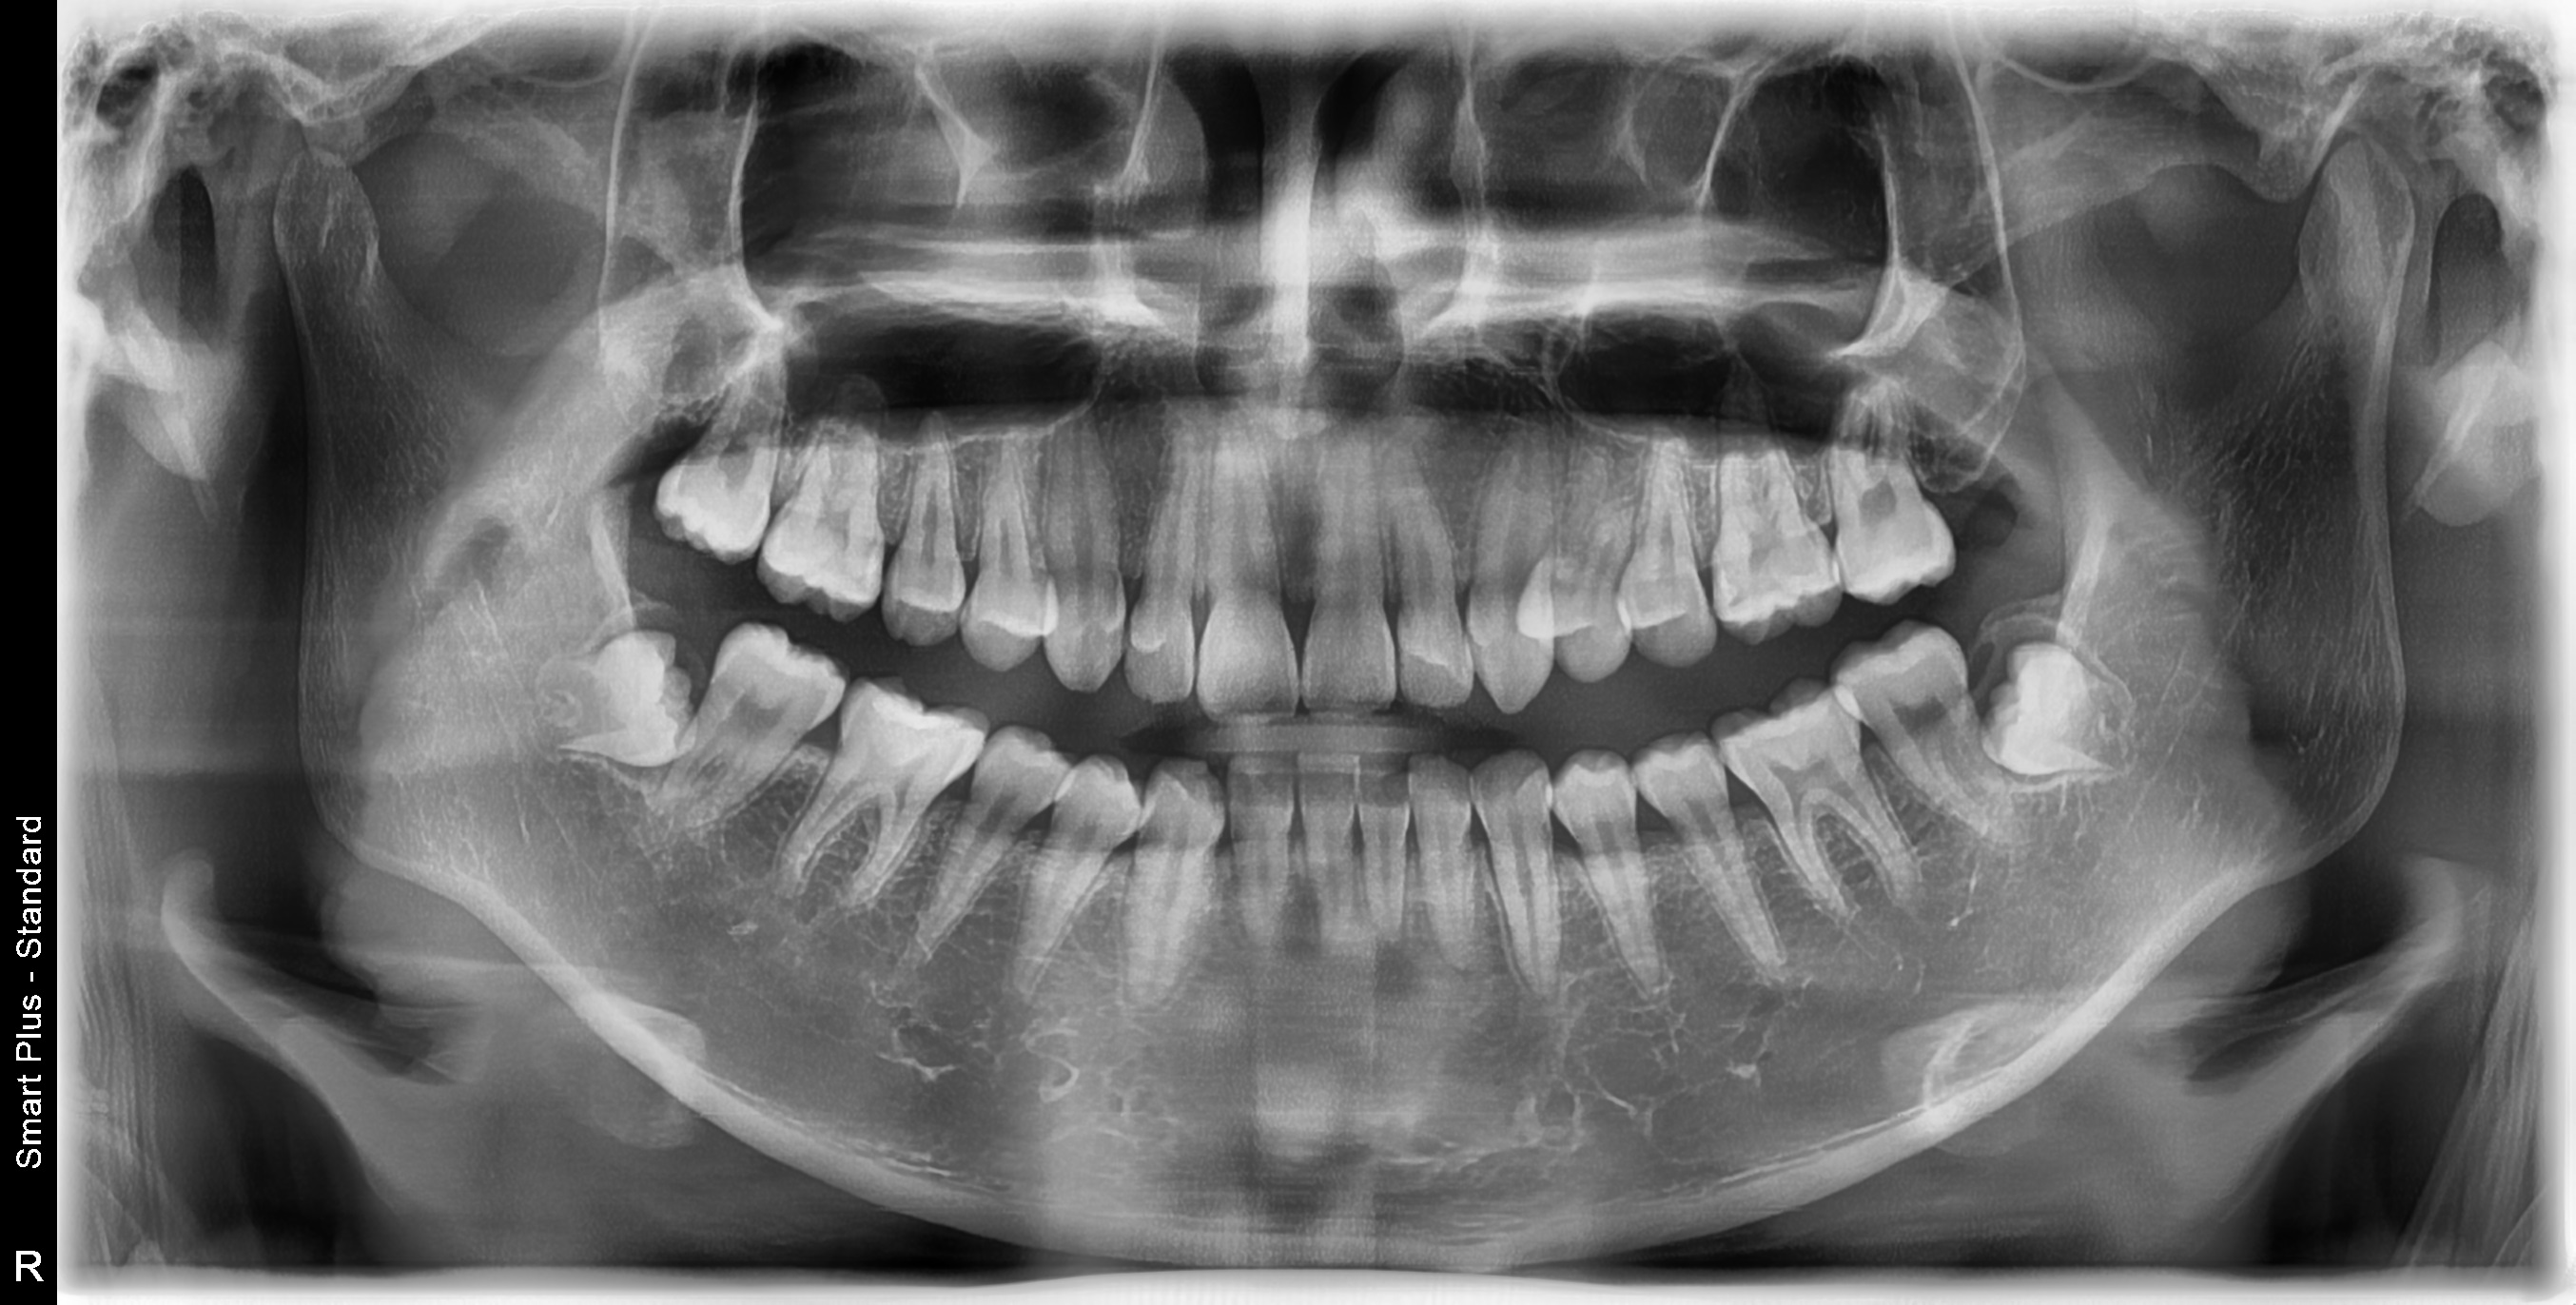

전체적인 치아상태 및 배열 안면윤곽 상태 등 정밀검사를 실시하였으며 아들이 고등학생이어서 성장판 검사는 별도로 하지 않았습니다.

정밀검사비용은 150,000원이 들었으며 전체교정비용은 590만 원으로 결정이 되었습니다. 치료방법에 따라 다르기 때문에 참고만 하시길 바랍니다.

● 검사결과 내용

치아뿌리상태는 좋고 어금니 가위교합(3개월정도)을 먼저 하고 어느 정도 진행이 되면 전체브라켓을 설치 후 과개교합(2개월정도) 교정을 실시한후 2차 정밀검사를 하고 발치여부를 판단하기로 하였습니다.

저는 상담 시 되도록이면 발치는 하지 않는 방향으로 한다고 말씀드렸고 다행히 2차 정밀검사 마친 후 발치 없이 전체교정을 시작할 수 있었습니다.

▼ 1차 정밀 검사 X-RAY